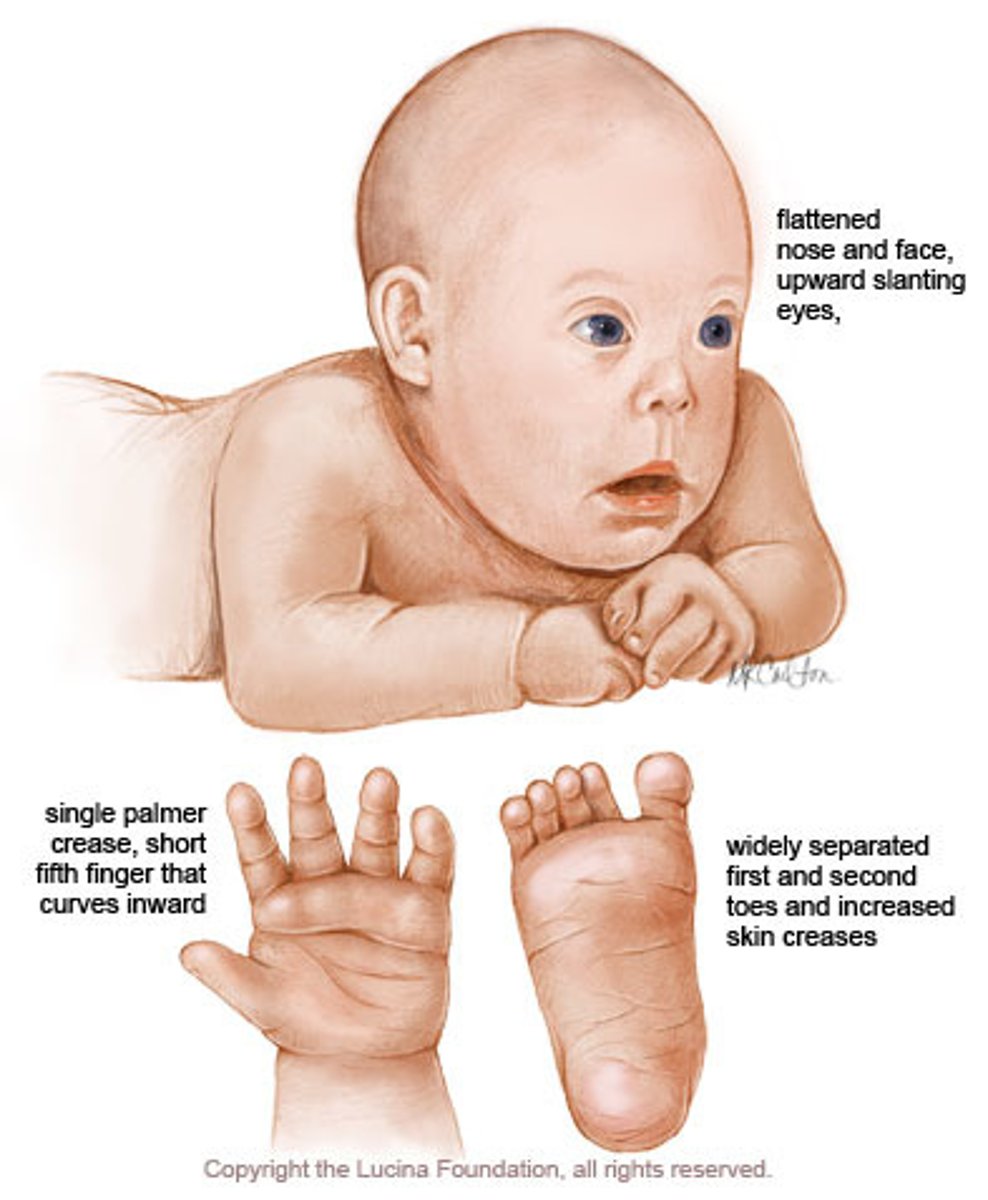

Which trisomy is associated with risk of VSD/ASD and subluxation of c-spine?

Trisomy 21 (Down Syndrome)